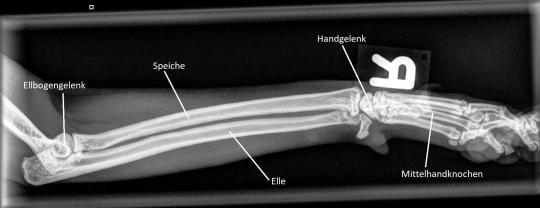

Leider erfüllt sich die Hoffnung, dass es sich nur um eine harmlose Verstauchung handelt, nicht - eine Woche später lahmt Barolo immer noch. Nun kann aber festgestellt werden, dass die Katze im mittleren Bereich des Unterarms schmerzhaft ist, weshalb die Region geröntgt wird: Die Elle ist in diesem Bereich fleckig verändert, was auf eine beginnende Auflösung des Knochens hinzuweisen scheint. Es ist zu befürchten, dass es sich um einen Knocheninfekt handelt, welcher sich Barolo bei einem Kampf zugezogen hat. Alternativ käme noch ein Befall mit Knochenkrebs in Frage, was aufgrund des Alters des Katers doch sehr unwahrscheinlich erscheint.

Zwei weitere Wochen später können wir endlich aufatmen und das Bein wird erneut geröntgt. Barolo geht es nun viel besser, er zeigt keine Schmerzen mehr, und auch die Röntgenaufnahme zeigt, dass sich die Veränderungen langsam zurückzubilden scheinen. Ganz offensichtlich hat es sich hier tatsächlich um einen (wohl durch einen Katzenbiss verursachten) bakteriellen Infekt der Elle gehandelt.